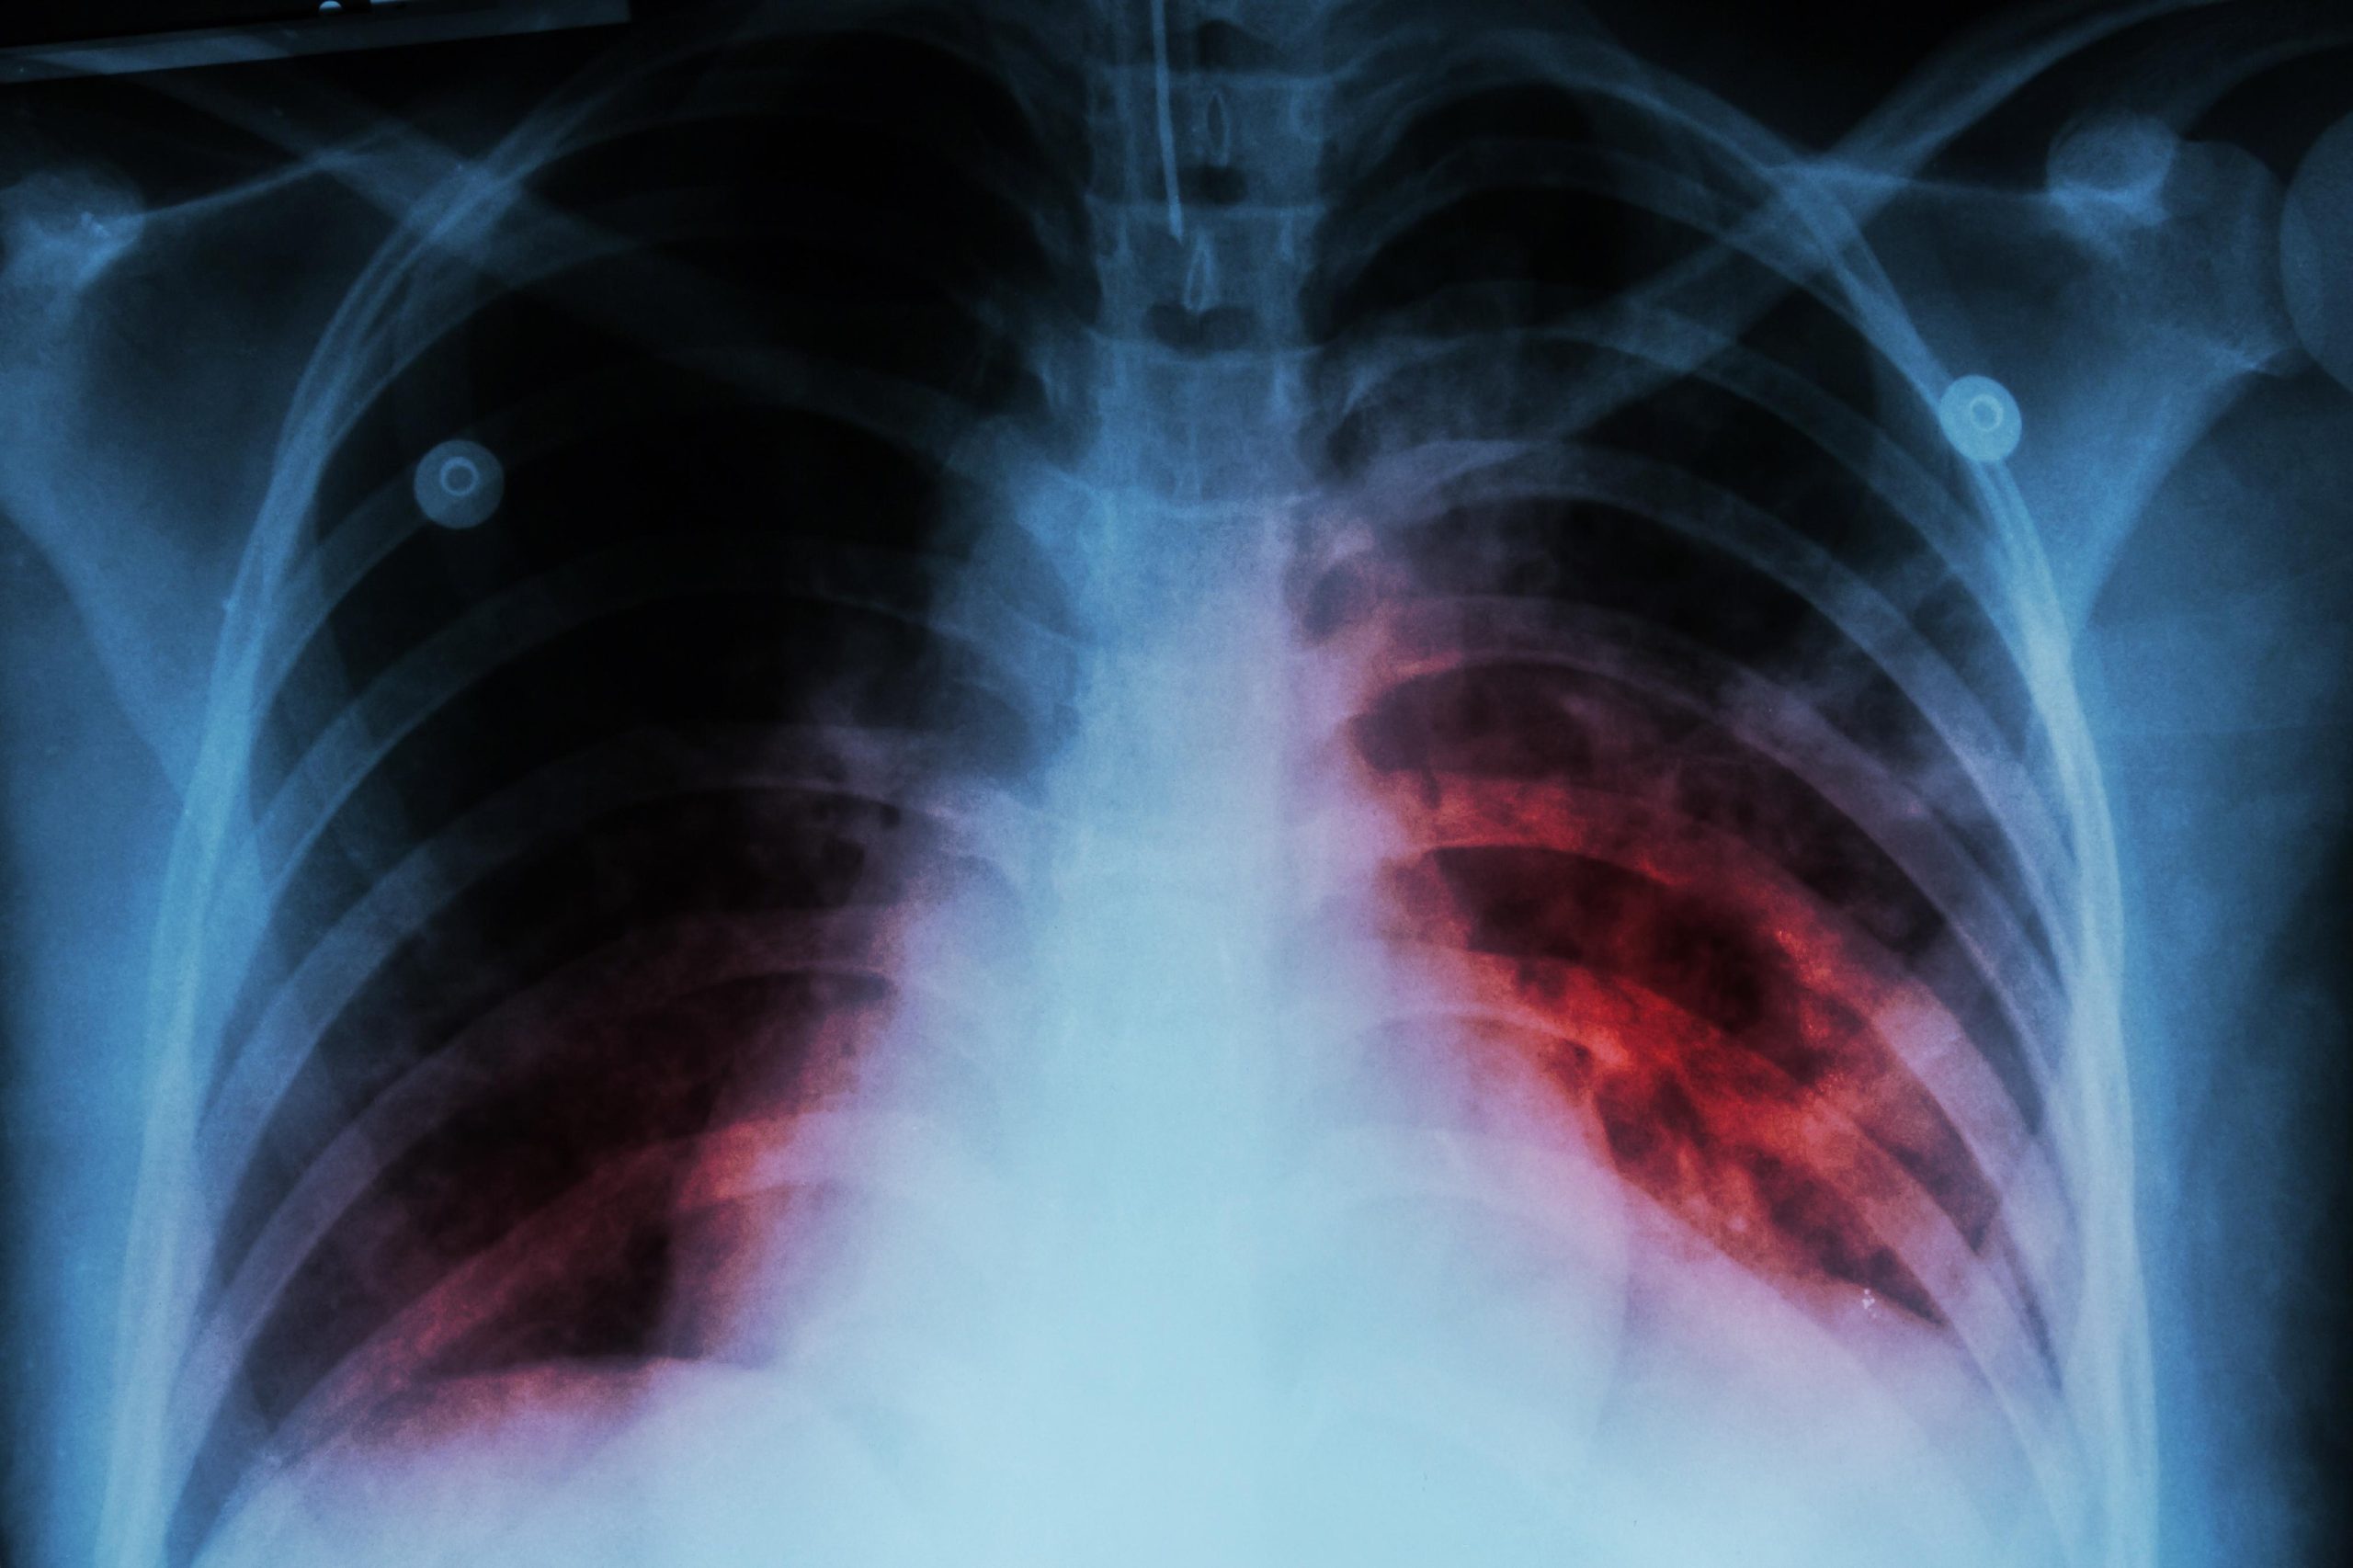

Las cifras de tuberculosis en Santander y Colombia son verdaderamente preocupantes. Según el Sistema Nacional de Vigilancia de Salud Pública SIVIGILA, en 2024 se registraron más de 35 mil casos de tuberculosis en el país, lo que representa un aumento del 25% en comparación con 2023.

Las preocupantes cifras la dieron a conocer este 10 de febrero Día Mundial de la Tuberculosis el Sistema Nacional de Salud, al indicar que el departamento de Santander fue el quinto más afectado con 1.391 casos en 2024, siendo Bucaramanga el municipio de mayor incidencia de tuberculosis, con 671 casos notificados. Le sigue Barrancabermeja, Floridablanca y Girón.

Lo más preocupante es que, en lo que va de 2025, Santander se ubica en el cuarto departamento más afectado, con 127 registros, de los cuales 78 son hombres y 49 son mujeres, la mayoría de los cuales viven en Bucaramanga.